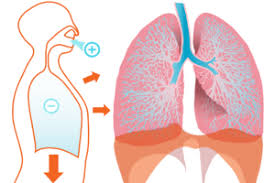

Charakteristisches Symptom bei einem Lungenemphysem ist die Atemnot besonders unter Belastung. Pneumothorax tritt auf wenn Luft in den Raum zwischen der Brustwand und der Lunge eintritt der als Pleuraspalt bezeichnet wird. Daher bei Atemnot und stechenden Schmerzen im Lungenbereich sofort die Rettung rufen.

Atemnot zuerst nur bei körperlicher Anstrengung später auch in Ruhe Husten verminderte Leistungsfähigkeit erhöhte Infektanfälligkeit. Befindet sich Flüssigkeit oder Sekret in der Lunge so wird der Körper als Schutzmechanismus versuchen dieses.

Die Oberfläche der Lunge verkleinert sich und die eingeatmete Luft wird nicht mehr vollständig ausgetauscht.